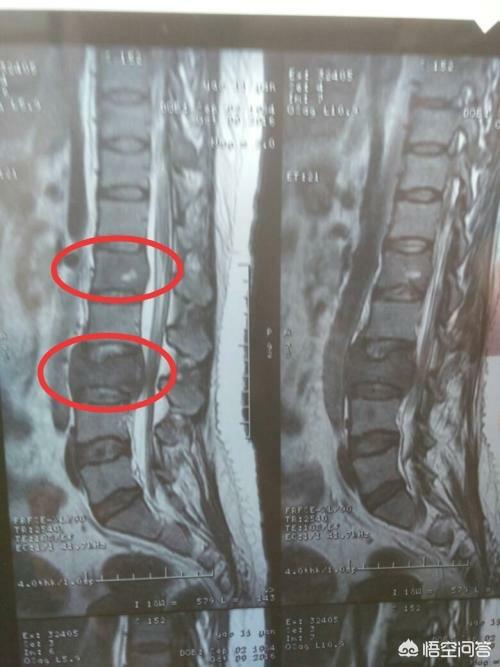

骨転移はどのような痛みに注意すべきですか?骨転移は悪性腫瘍の末期によく見られる症状で、体の他の部位にある原発腫瘍が血液やリンパ液の経路を通って骨に転移し、骨転移を形成することを指します。骨転移は、正常な骨組織が破壊され、腫瘍組織に置き換わっていることを示す。骨転移は病変の特異性により、溶骨型、造骨型、混合型の3つに分類される。骨転移の好発部位は中軸骨(脊椎、骨盤)、肋骨、下部骨幹部で、特に中軸骨が最も多く、これはこの部位の血液供給の特徴と関係しています。下の円のように骨転移が多発し、脊椎の状態が悪い。

胸椎に発生した骨転移性癌を示す。

46歳の男性が、腰の持続的な痛みのために受診した症例があった。腰痛は椎間板ヘルニアと考えられた。レントゲンを撮ったが異常は見られなかった。わずかな骨破壊を起こす骨転移はレントゲンでは見えないし、椎間板ヘルニアもレントゲンでは見えない。だから、転移の可能性については特に考えなかった。1週間後、それでも改善が見られないのでCTを撮りに来たところ、腰椎が食べられていた。 このような画像を見て、画像診断医は転移の可能性を考えるに違いないと思い、胸部CT検査をするよう患者に勧めたところ、案の定、肺に腫瘤があり、肺がんの骨転移と考えられ、後日病理検査で確認された。